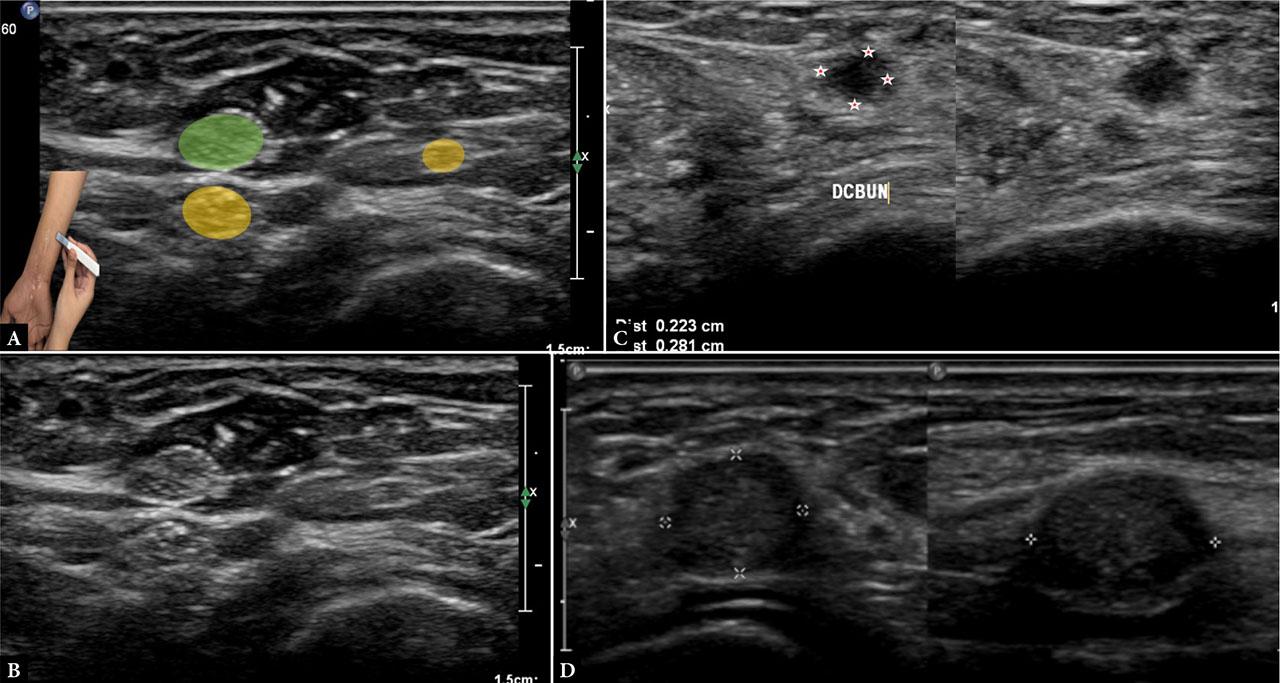

The dorsal cutaneous branch of the ulnar nerve (DCBUN) is a terminal branch that arises from the ulnar nerve in the distal forearm. It passes volar to the ulna and dorsal to the flexor carpi ulnaris tendon before piercing the antebrachial fascia to become subcutaneous. From there, the nerve courses superficially along the dorsoulnar aspect of the hand and provides sensory supply to the dorsum of the fifth finger, the dorsoulnar portion of the fourth finger, and adjacent hand regions. Injuries to the DCBUN may be traumatic or iatrogenic. The nerve is particularly at risk during surgical approaches to the subcutaneous border of the ulna, such as those employed for open reduction and internal fixation of ulnar fractures. Sonographically, it can be identified in the distal forearm as it arises from the ulnar nerve in close association with the flexor carpi ulnaris(13) (Fig. 6).

Images A and B demonstrate the normal dorsal cutaneous branch of the ulnar nerve (smaller yellow circle) arising from the ulnar nerve (yellow circle) in the distal forearm (inset). The ulnar nerve lies deep to the flexor carpi ulnaris tendon (red) and gives rise to the DCBUN, which wraps over the ulna and travels in the subcutaneous plane of the dorsal forearm. Image C demonstrates neuroma formation within the DCBUN (asterisk) in a patient with a glass-cut injury in the distal forearm. Image D shows a hypoechoic mass along the DCBUN (asterisk) in the distal dorsal forearm in orthogonal planes, consistent with a peripheral nerve sheath tumor, presenting as a hypoechoic fusiform lesion with the DCBUN seen as a tail at both ends